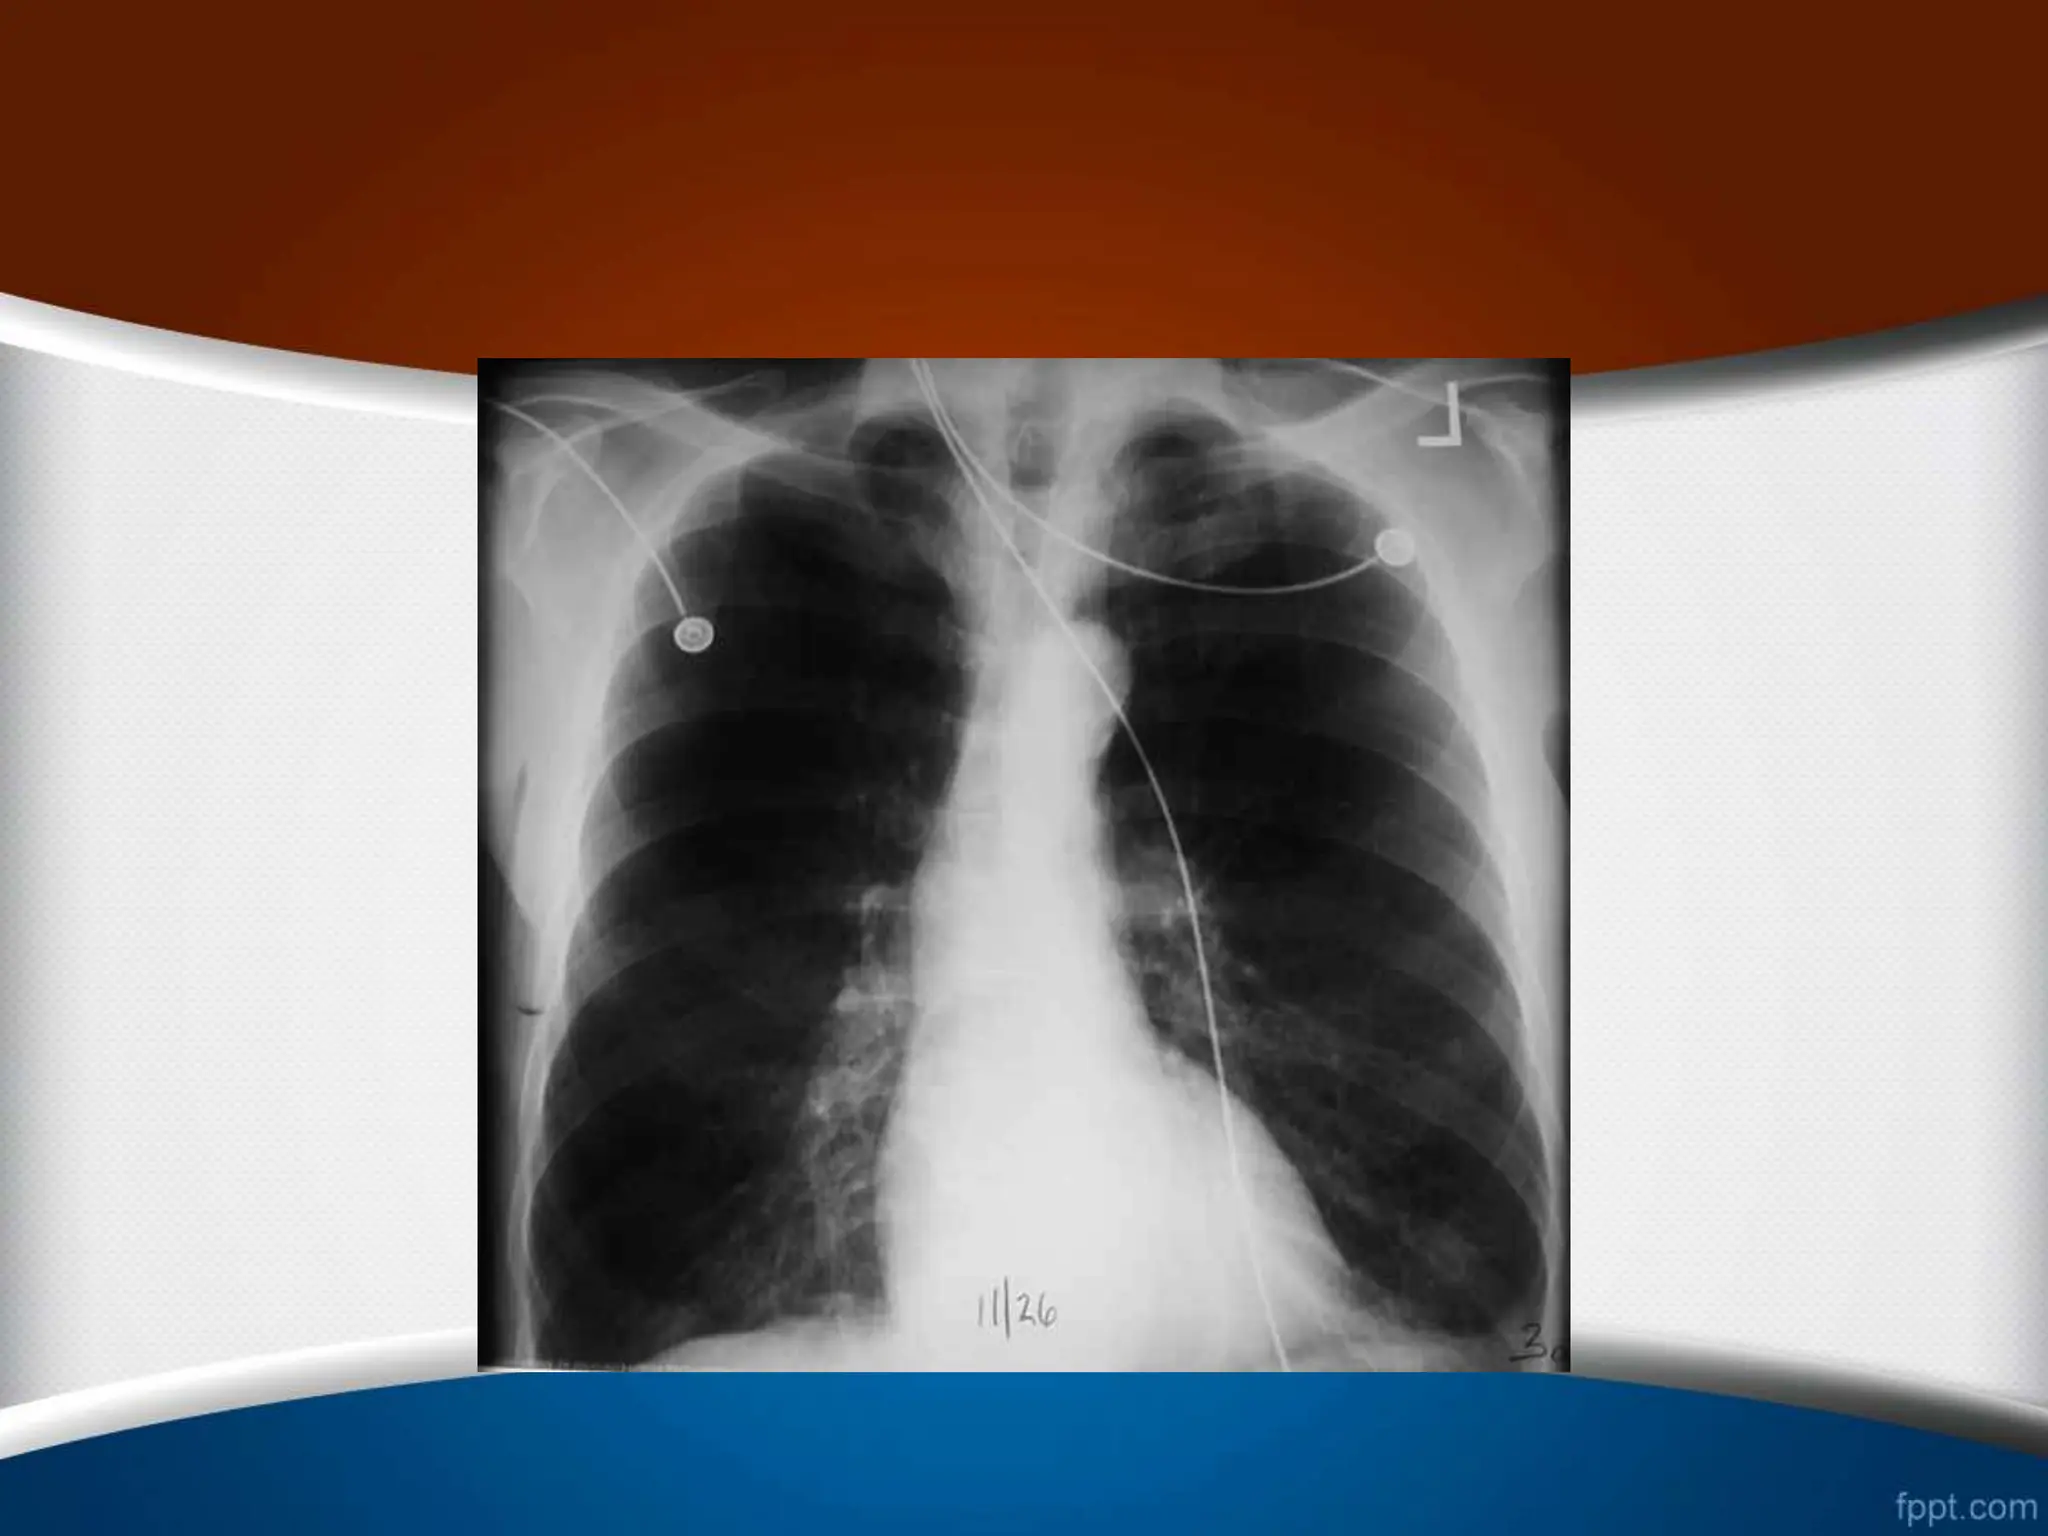

• #79 در گرافی سمت چپ، نسبت کاردیوتوراسیک افزایش یافته است. توزیع مجدد عروق ریوی دیده می شود ودر اطراف ناف ریه مقطع شریان (فلش قرمز) از مقطع برونش (فلش آبی) بیشتر است.